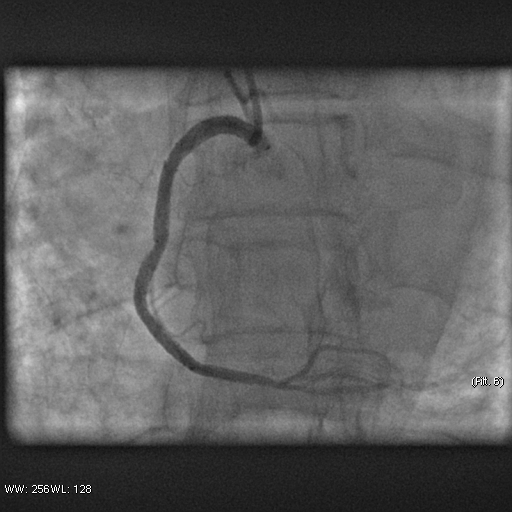

Stenosis of the anterior interventricular artery in the 6.7 segment is 95%. Stenosis of the orifice of the diagonal artery of the 1st order is 95%. Stenosis of the circumflex artery in the 13th segment is 40%. During coronary angiography, pronounced spasm is noted in the 2nd segment of the right coronary artery with complete occlusion of the artery lumen. After stopping the spasm, coronary angiography shows a spiral (spontaneous) dissection of the right coronary artery from segments 1 to 3.

A guiding catheter JR 3.5 6Fr was inserted along a 0.035" 260.0 cm guidewire. The guidewire was removed. The right coronary artery was catheterized. A 7Fr Y-click connector (complete with an insertion device and a guidewire rotation device) was connected to the guiding catheter. A coronary guidewire Whisper ES 0.014" 190 cm, Asahi Gaia Third 0.014" 190 cm was inserted and brought into the orifice of the right coronary artery. The guidewire was inserted beyond the lesion zone of the right coronary artery in segment 2, then into the distal sections. Wilma NC 2.00*20.0 mm and Wilma NC 3.00*15.0 mm balloon catheters were inserted alternately along the coronary guidewire - predilation of the lesion zone of the right coronary artery in segment 2 was performed. Inflation of balloon catheters 14 atm. with an inflator, the balloon catheters are deflated and removed. A stent is inserted along the coronary guidewire - the Yukon Chrom PC 3.0 * 28.0 mm system, Yukon Chrom PC 3.0 * 28.0 mm, Cid Cre 8 3.50 * 25.0 mm, Cid Cre 8 4.0 * 16.0 mm - the stent is implanted in the lesion area of the right coronary artery in the 2nd segment. Inflation of the balloon catheter 9-16 atm. with an inflator, the balloon catheter is deflated and removed. Control coronary angiography - blood flow in the stenting zone is TIMI3, there are no signs of dissection or stent dislocation.